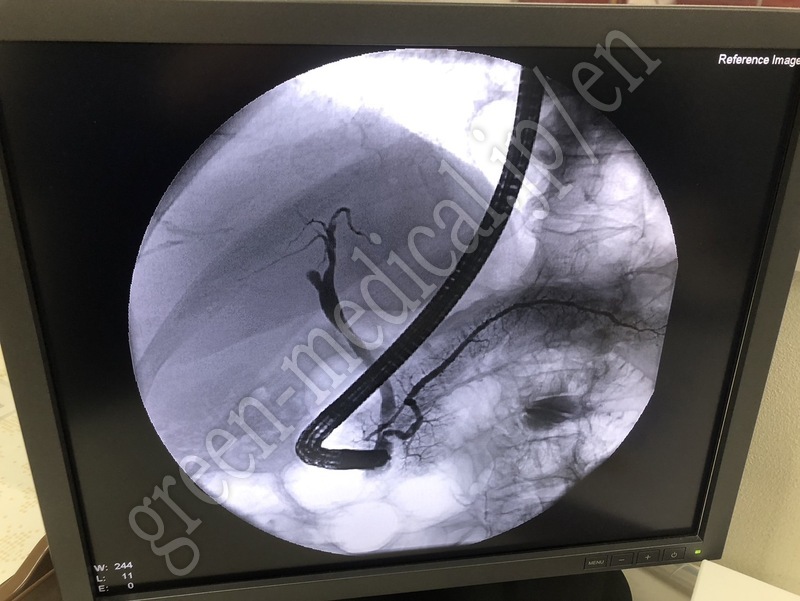

Lithotripter Delta Ⅱ

Fabricante

Dornier Medtech Systems

Tipo

Delta Ⅱ

Inventario

116961